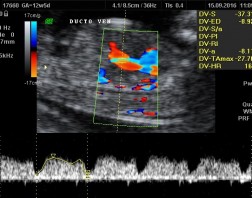

Este exame tem como objetivo avaliação precoce de algumas alterações anatômicas fetais e rastreamento das cromossomopatias mais comuns, como trissomia 21 (síndrome de Down), trissomia do 18 (síndrome de Edwards) e trissomia do 13 (síndrome de Patau), através da análise de alguns marcadores como translucência nucal, osso nasal e ducto venoso.

Avalia-se também a Dopplerfluxometria das artérias uterinas com o objetivo de rastrear as pacientes com maior risco de desenvolver pré-eclâmpsia ou restrição de crescimento fetal.